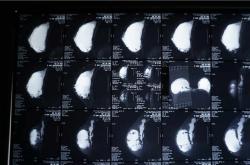

胸部奥美定取出修复中心,专业胸部奥美定取出20余年,取出同时,植入自体脂肪。